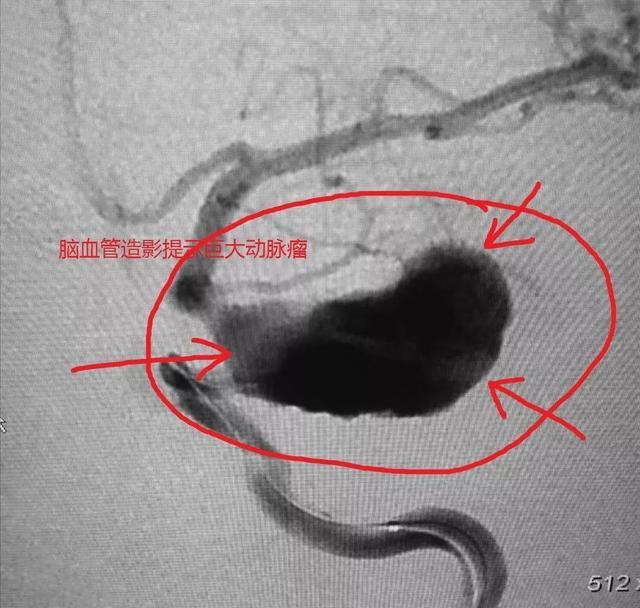

在第三条我已经说过头颅是不需要做常规CT的,因为意义不大。但你要知道,有一部分自发性脑出血患者,往往是因为脑动脉瘤破裂而出血的,而一般的CT是看不见动脉瘤的,有人说磁共振行不行?也不行,那怎么办?

如果你很土豪,可以做CT动脉造影,或者直接介入颅内血管造影。这是排查血管瘤的方式,其他检查做了达不到目的。